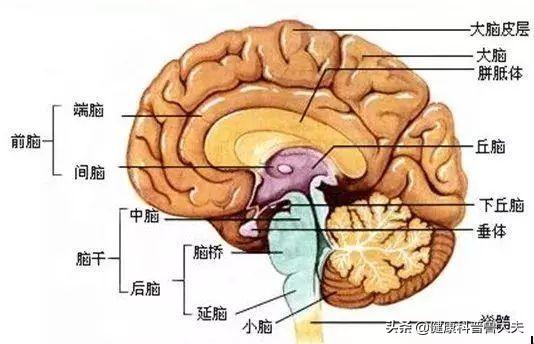

Notre cerveau gère presque toutes les fonctions de notre corps et est connu comme le commandant du corps. Le cerveau dépend du sang pour transporter l'oxygène et les nutriments dont il a besoin. Lorsque les vaisseaux sanguins sont bloqués pour diverses raisons, le cerveau est incapable d'obtenir de l'oxygène et des nutriments et meurt, entraînant la perte de fonctions de notre corps, ce qui est appelé infarctus cérébral. Les fonctions des différentes parties du cerveau étant différentes, les patients auront des séquelles plus ou moins importantes selon la localisation et l'étendue de la nécrose. Certaines personnes peuvent n'avoir qu'un léger vertige et découvrir qu'elles ont subi un infarctus cérébral lorsqu'elles se rendent à l'hôpital pour un examen (la plupart des patients atteints d'infarctus cérébral lacunaire sont découverts au cours de l'examen). Certains patients garderont des séquelles telles que l'hémiplégie, l'immobilité, la cécité, le retard mental, voire la mort.

Examinons tout d'abord le terme "infarctus cérébral léger". En général, si l'on classe le degré de la maladie, on trouve les expressions "léger", "modéré" ou "grave", et avec l'infarctus cérébral, cela signifie que le degré de l'infarctus cérébral est relativement faible. L'infarctus cérébral est le nom abrégé de la maladie "infarctus cérébral" ou "infarctus cérébral", l'infarctus cérébral et l'infarctus cérébral sont des noms différents de la même maladie, seuls les grands et les petits noms sont différents. L'infarctus cérébral est l'infarctus des cellules cérébrales, la signification de la mort des cellules cérébrales, les cellules cérébrales sont l'unité de base du tissu cérébral, le tissu cérébral est divisé en cerveau, mésencéphale, cervelet, tronc cérébral.

Chaque tissu cérébral et chaque zone fonctionnelle sont différents, tout comme le rôle qu'ils jouent.

Par exemple, l'hémisphère gauche du cerveau régit les mouvements du côté droit du corps et l'hémisphère droit contrôle les mouvements du côté gauche du corps ; le lobe préfrontal du cerveau est responsable de la pensée, de la planification et est associé aux besoins et aux émotions de l'individu. Le lobe pariétal du cerveau - répond aux sensations de douleur, de toucher, de goût, de température, de pression ; cette zone est également associée aux mathématiques et à la logique. Lobe temporal du cerveau - Responsable du traitement des informations auditives, il est également associé à la mémoire et aux émotions. Lobe occipital du cerveau - Responsable du traitement des informations visuelles. Le système limbique du cerveau est impliqué dans la mémoire et dans les aspects comportementaux et émotionnels. Il est impliqué dans tous les aspects du corps humain tels que les sensations, les mouvements, les émotions et la mémoire.

Par exemple, la fonction du cervelet est étroitement liée à la fonction d'équilibre du corps. La fonction du tronc cérébral est principalement de maintenir la vie de l'individu, y compris le rythme cardiaque, la respiration, la digestion et d'autres fonctions physiologiques importantes.

Chaque partie du tissu cérébral a donc une fonction différente des cellules cérébrales. Si des cellules cérébrales meurent dans cette partie, la fonction de cette partie est diminuée ou perdue. Par diminution, on entend que la zone de mort cellulaire est plus petite, et par perte, on entend que la zone de mort cellulaire est plus grande.